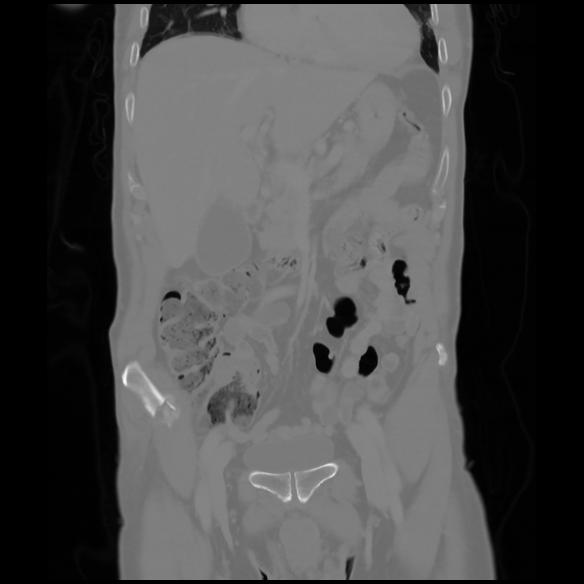

6 CUERPO,CE,Coronal,3.000,CUERPO,Coronal,